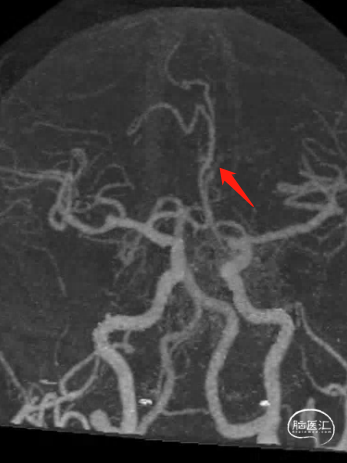

急诊头颅MRI+MRA示:双侧额叶少许小缺血灶;脑动脉硬化,伴左侧大脑前动脉纤细及多组脑动脉局限性狭窄。

CTP示:右侧额颞顶枕叶、左侧额叶Tmax稍延长,提示侧枝代偿尚可。

DSA:

3D测量。